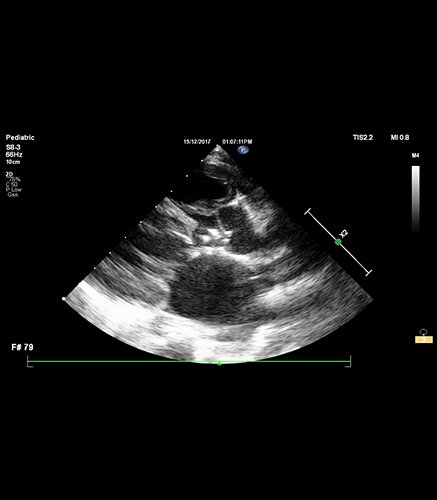

2-D & 3-D TRANS-OESOPHAGEAL ECHOCARDIOGRAM (TEE)

Trans-esophageal echocardiography (TEE) is a specialized ultrasound technique that provides detailed images of the heart similar to GI Endoscopy. A small, flexible probe with an ultrasound transducer is inserted through the mouth and into the esophagus, allowing a clearer view of the heart's structures (especially the posteriorly located ones) and blood flow.